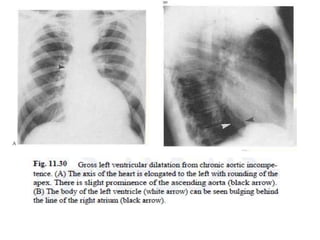

• In chronic aortic regurgitation: The plain

radiograph demonstrates a large heart with a

predominantly left ventricular configuration.

The heart size reflects the severity of the

disease.

• The ascending aorta and often the aortic arch are

large and can sometimes be visualized as a bulge

on the right of the mediastinum.